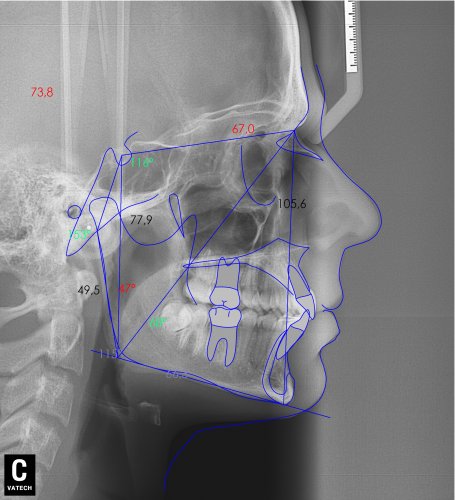

Paciente de 14 años, acude a nuestra consulta por dientes superiores proclinados hacia delante y apiñamiento. El paciente presenta una full clase 2, sobremordida y dientes inferiores proclinados. Decidimos colocarle brackets Damon y microtornillos en maxilar superior para distalizar las muelas. La duración del tratamiento fue de 24meses, y ahora lleva 1 año de contención. El paciente se pone la férula Essix superior 1noche/2 y la de abajo 1noche/semana para mantener.